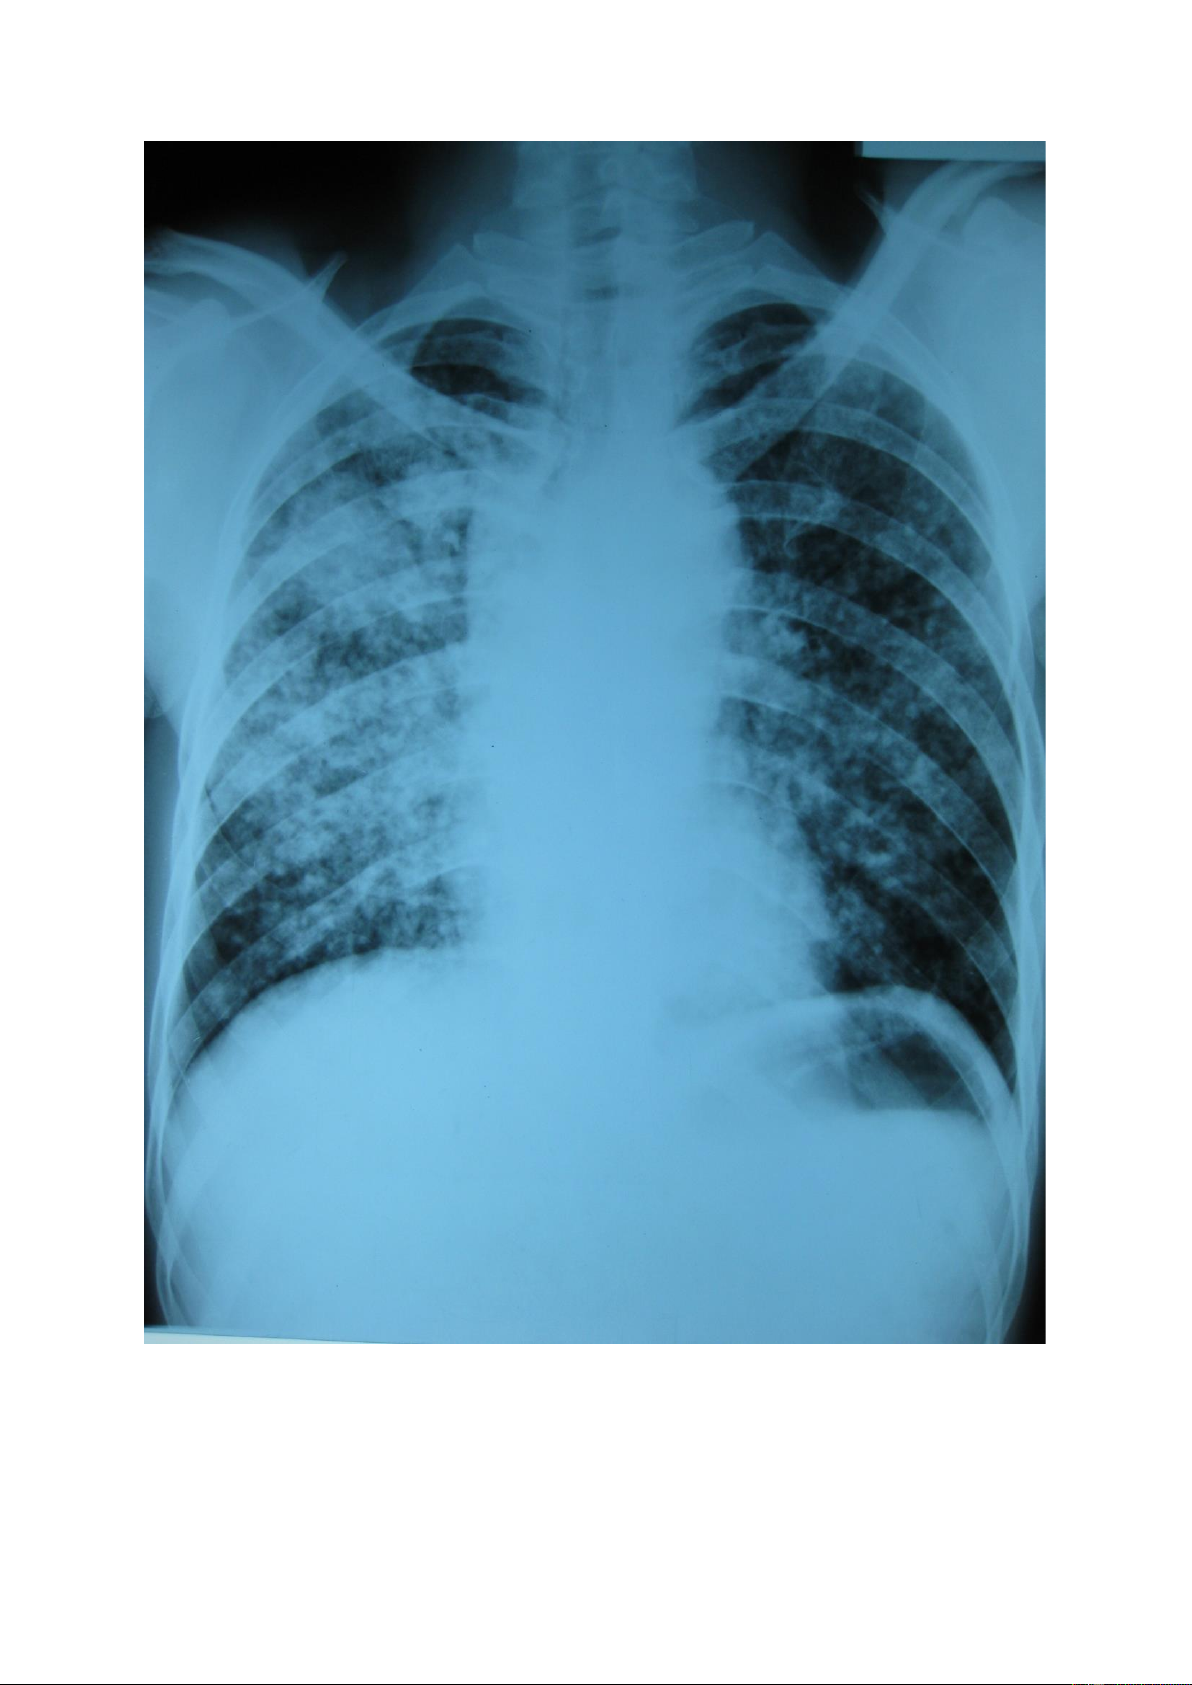

Nốt mờ lớn: là tổn thương có kích thước >3mm và < 3cm, số lượng có thể đơn

độc hoặc nhiều, kích thước có thể đều hoặc không đều, đậm độ cản quang khác nhau. lOMoAR cPSD| 22014077 lOMoAR cPSD| 22014077 1.3.